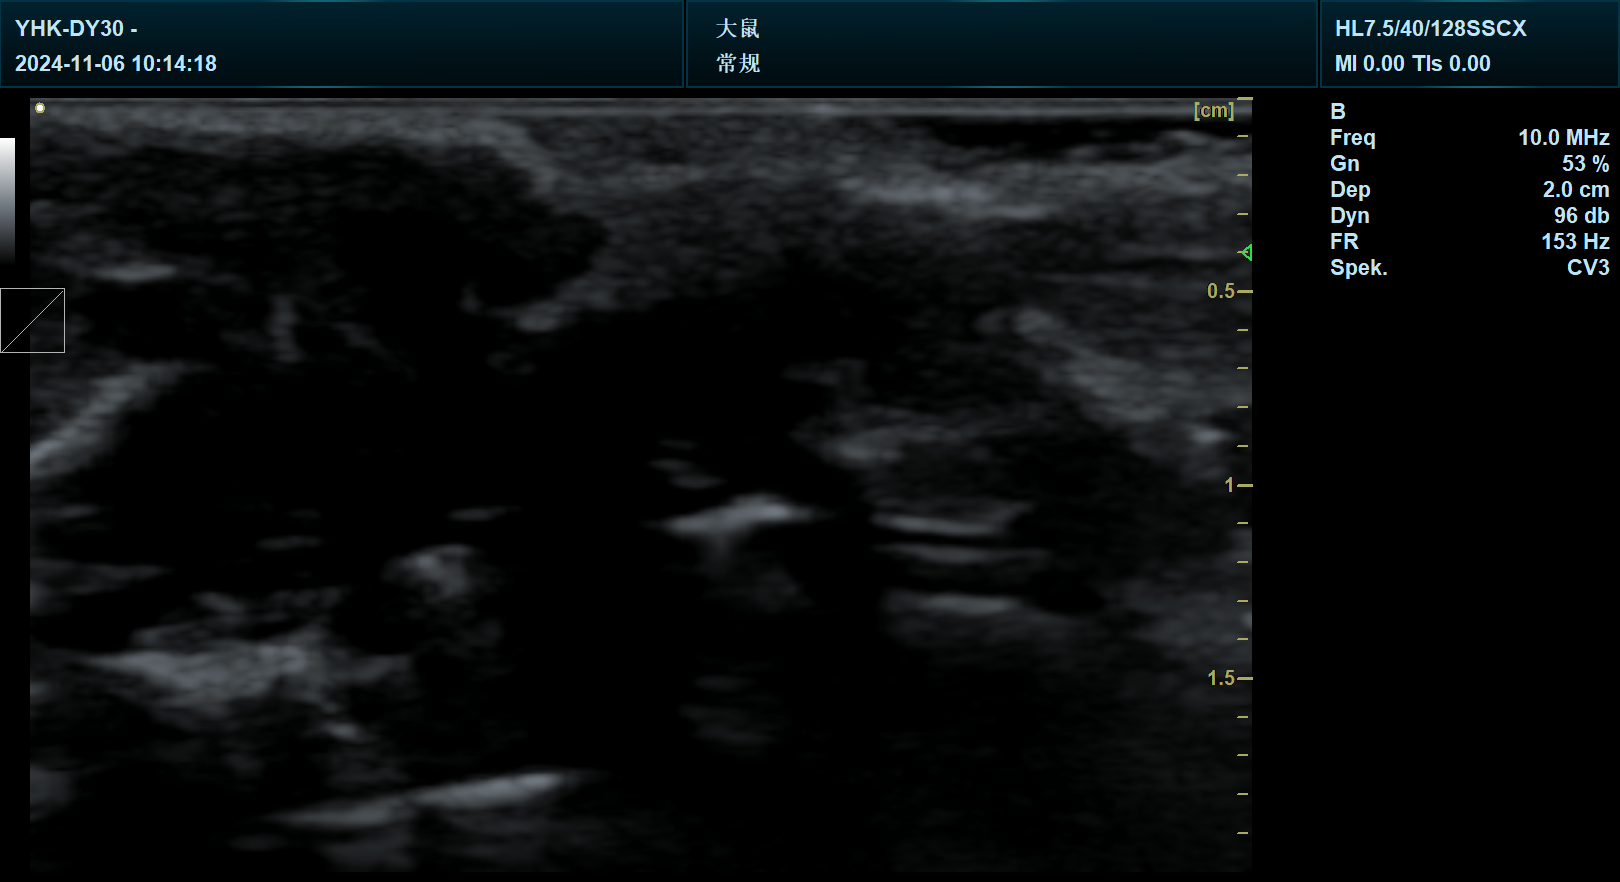

临床前——超声:引导注射

高频超声波也可用于引导注射到小鼠解剖结构内的特定区域。对于关节内的注射,最近显示这比使用传统的解剖标志具有更高的成功率。